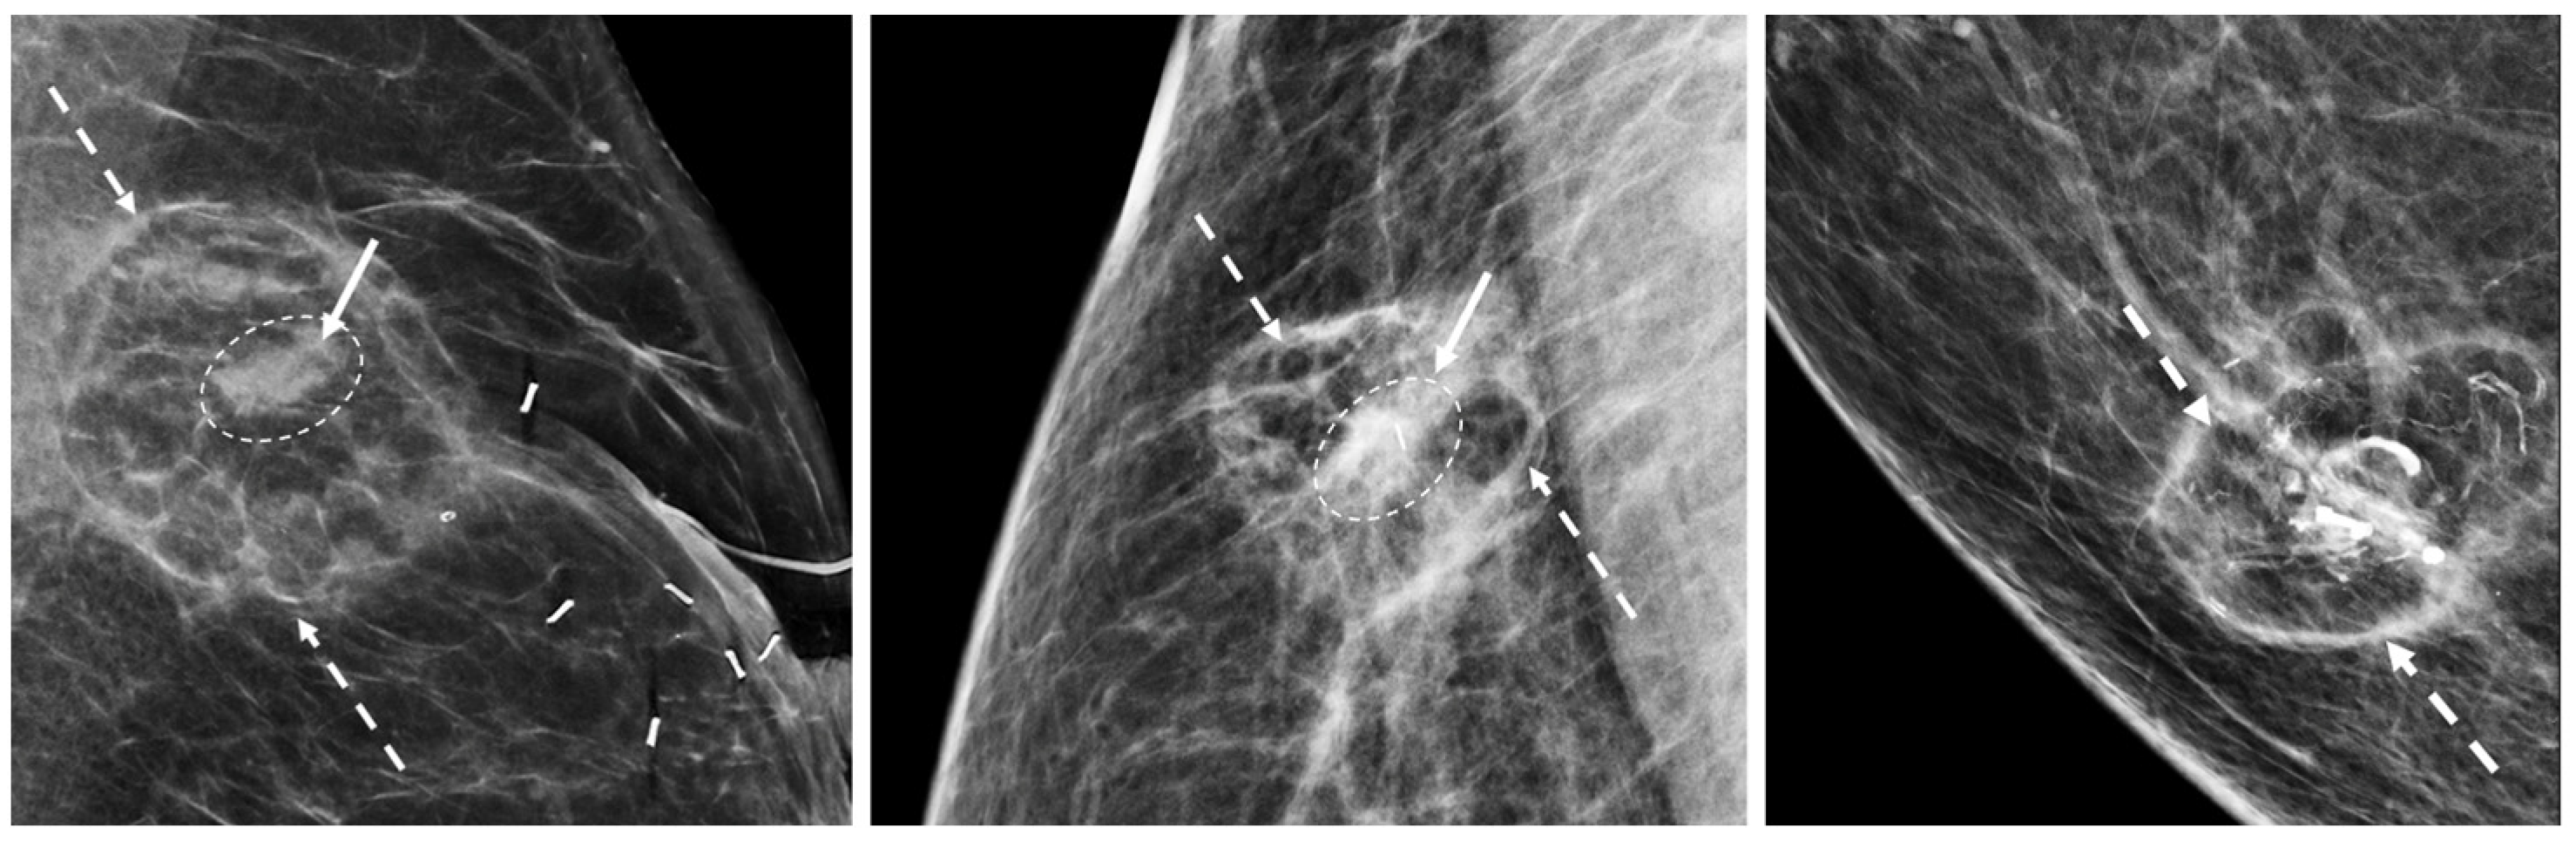

Digital Mammography. Breast cancer staging should include bilateral digital diagnostic mammograms (preferably 3D mammograms or tomosynthesis) to evaluate the extent of disease. Although cryoablation is generally performed under ultrasound or CT-scan guidance, high-quality mammography might reveal additional areas of cancer in the same region of the breast (multifocal cancer) or in a different region of the breast (multicentric cancer) that might impact patient selection or alter the cryoablation treatment plan. Multicentric and multifocal breast cancer is generally regarded as a contraindication to cryoablation. Pre-treatment assessment of the mammograms should seek the detection of spiculations (radial tumor extensions) and/or microcalcifications that might reach beyond the main tumor mass and require incorporation in the cryoablation treatment zone (Figure 1). Since mammography is the only imaging study that reliably shows microcalcifications, mammography plays a particularly important role in determining disease extent when suspicious microcalcifications are part of the disease process. Consequently, patients who are generally opposed to obtaining screening mammograms should be encouraged to have at least one set of pre-treatment diagnostic mammograms to exclude the presence of suspicious microcalcifications that could impact patient selection and/or treatment planning.

Figure 1.

Mammogram showing density corresponding to a palpable mass (see dashed lines) as well as suspicious microcalcifications (arrows) and inset image showing magnified view of white punctate calcifications extending beyond the palpable mass.

Generally, a single biopsy site marker is sufficient for marking the site of most breast cancers. However, patients with a wide span of disease may benefit from placement of two or more ultrasound-visible markers to outline or bracket the borders of the cancer to improve targeting of the cryoablation treatment (Figure 7).

Figure 7.

Mammogram showing the metal components (indicated arrows) of two ultrasound-visible biopsy site markers on opposite sides of the original metal biopsy site marker (encircled by hash marks) that was placed at the time of the diagnostic needle biopsy. The original biopsy site marker was not an ultrasound visible.